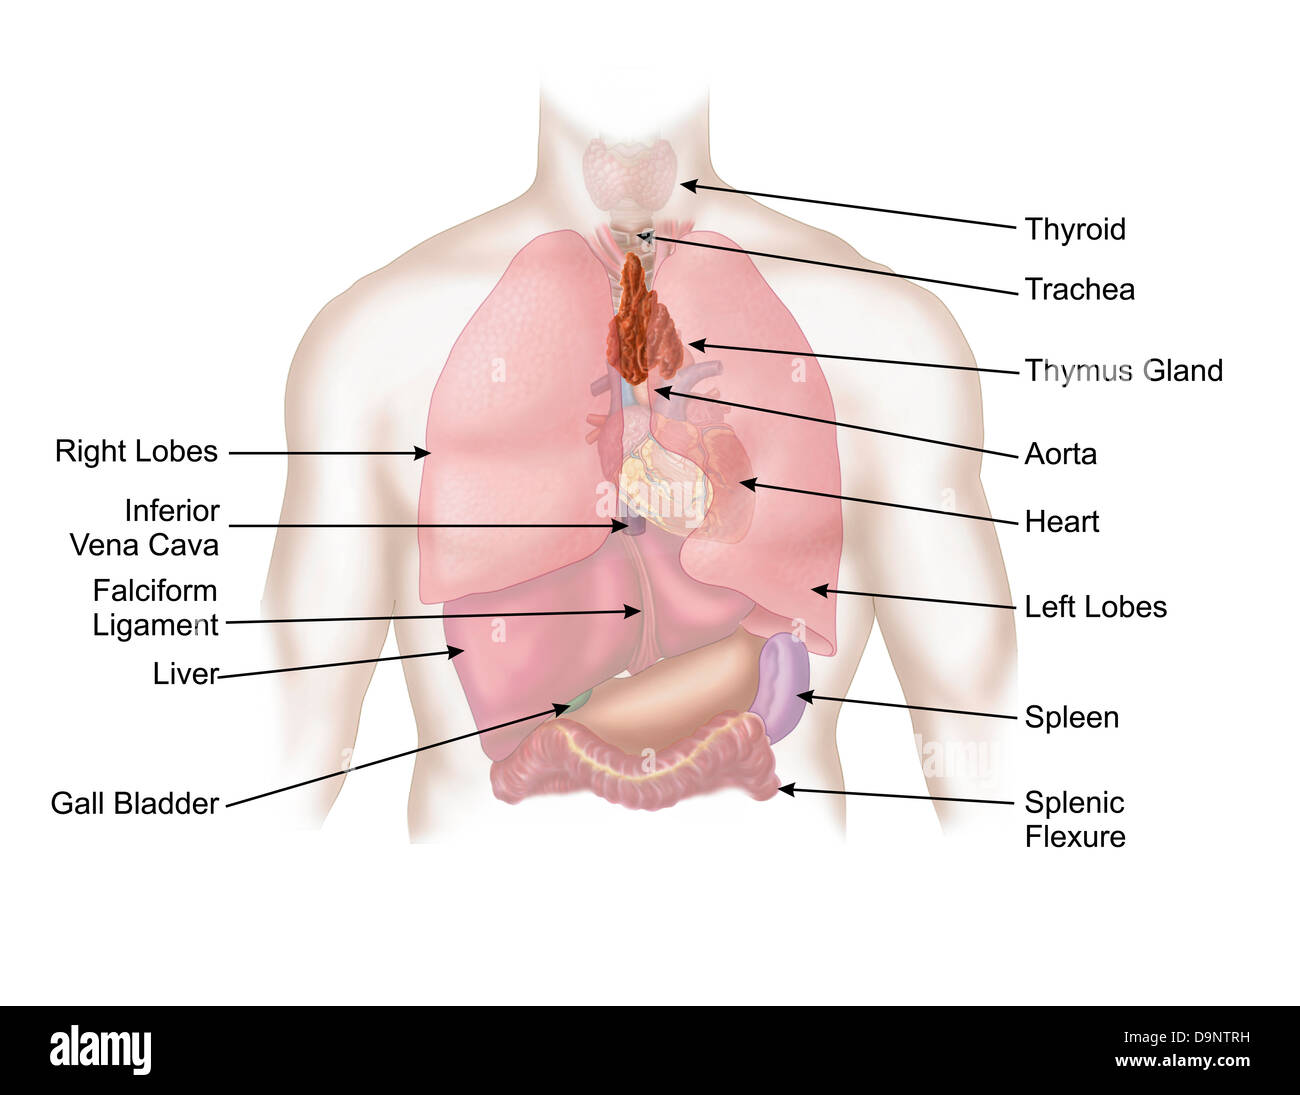

Medical illustration of human respiratory and digestive system. Stock Photohttps://www.alamy.com/image-license-details/?v=1https://www.alamy.com/stock-photo-medical-illustration-of-human-respiratory-and-digestive-system-57643477.html

Medical illustration of human respiratory and digestive system. Stock Photohttps://www.alamy.com/image-license-details/?v=1https://www.alamy.com/stock-photo-medical-illustration-of-human-respiratory-and-digestive-system-57643477.htmlRFD9NTRH–Medical illustration of human respiratory and digestive system.